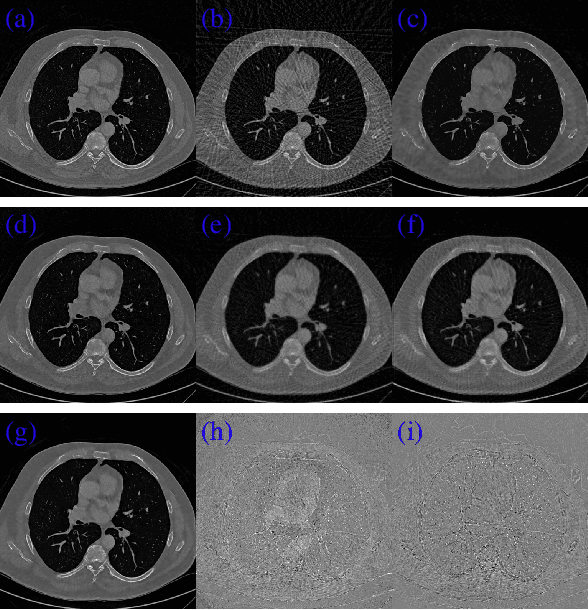

CT image reconstruction from incomplete data, such as sparse views and limited angle reconstruction, is an important and challenging problem in medical imaging. This work proposes a new deep convolutional neural network (CNN), called JSR-Net, that jointly reconstructs CT images and their associated Radon domain projections. JSR-Net combines the traditional model based approach with deep architecture design of deep learning. A hybrid loss function is adopted to improve the performance of the JSR-Net making it more effective in protecting important image structures. Numerical experiments demonstrate that JSR-Net outperforms some latest model based reconstruction methods, as well as a recently proposed deep model.